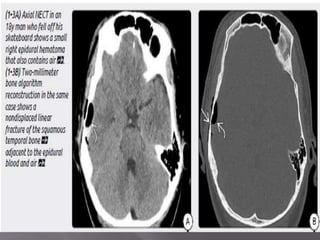

1) Epidural hematoma- two types : arterial EDH and

venous EDH. EDH r uncommon but r potentially

lethal. 90% EDH r arterial , 10% r venous. Venous

EDH r sec. to a fracture that crosses dural venous

sinus (transverse/sig , SSS)

a) Arterial EDH – d/t direct trauma to skull that

lacerates an adjacent artery(mc’ly-mma)

mostly unilateral and supratentorial. Squamous

portion of temporal bone is the most common site.

Biconvex in shape, doesnt crosses suture line, but

if fracture crosses suture line……

 Imaging- Look for other comorbid lesions such

as "contre-coup" injuries, tSAH, and secondary

brain herniations, all of which are common

findings in patients with EDHs.

 CT - classic (arterial) EDHs is a hyperdense (60-

90 HU) biconvex extraaxial collection (2-18).

Presence of a hypodense component ("swirl"

sign) is seen in about one-third of cases and

indicates active, rapid bleeding with

unretracted clot.

“Buckling" the gray-white matter interface

inward.

Air in an EDH occurs in approximately 20% of

cases and is usually associated with a sinus or

mastoid fracture.